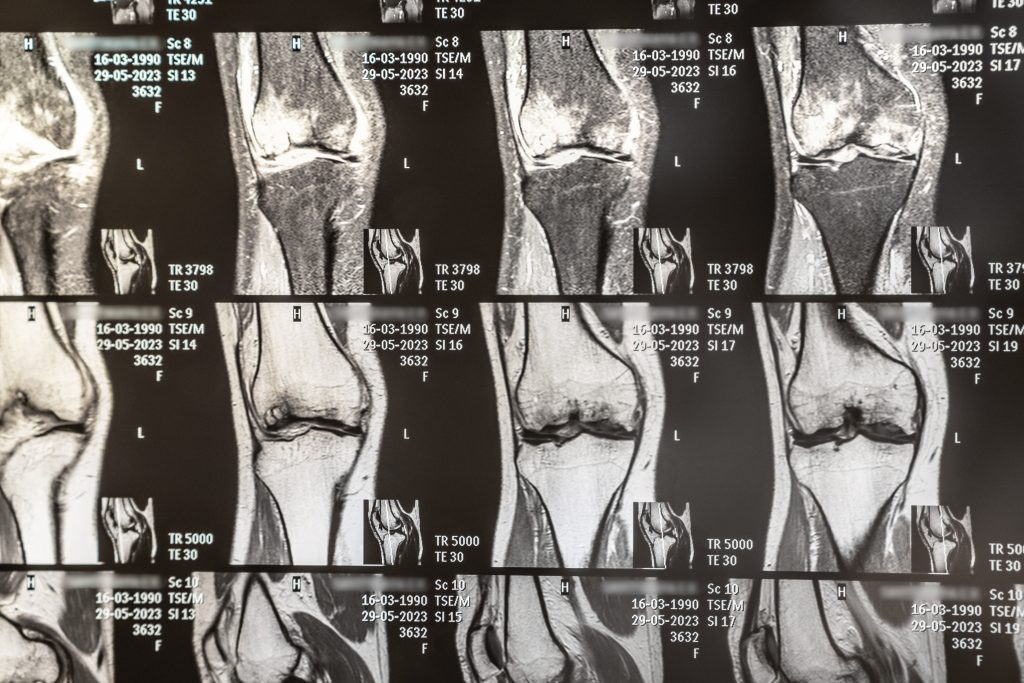

A ressonância magnética é, sem dúvida, o padrão ouro para diagnósticos ortopédicos devido à sua precisão, segurança e capacidade de detectar alterações em tecidos moles que outros exames não conseguem identificar.

Seja para diagnosticar lesões, planejar cirurgias ou monitorar tratamentos, esse exame é uma ferramenta indispensável na ortopedia moderna.

Precisa realizar seu exame com tecnologia de ponta e atendimento humanizado? A Clima Clínica oferece equipamentos modernos e profissionais especializados para cuidar da sua saúde. Agende agora mesmo!